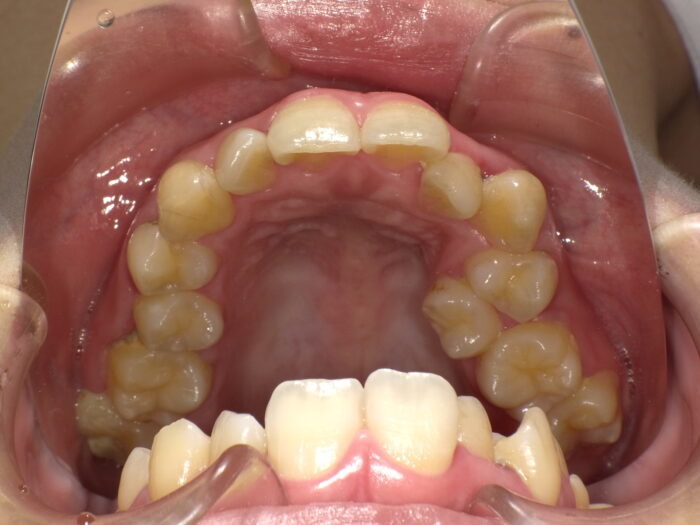

マウスピース型矯正装置(インビザライン)で、抜歯が必要かそうでないかは、奥歯のかみ合わせの位置が重要になります。正しい奥歯の位置関係は、写真のように下の奥歯が前方、上の奥歯が後方に出ている状態で、それぞれの凸凹が噛み合っています。

正しい噛み合わせ、または軽いズレの場合は歯を抜かずに、矯正治療が可能なことが多いです。